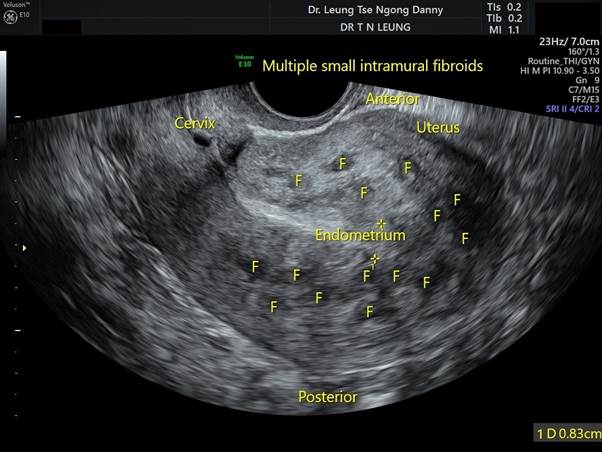

Uterine fibroids are non-cancerous growths that develop in or around the uterus. They are very common in women aged 25–50.

- Multiple fibroids